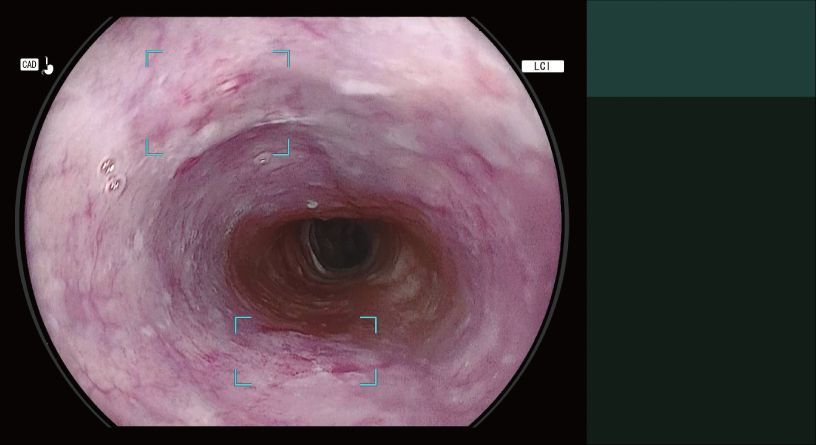

Detection Box

Indicates the area where this software suspects that a lesion is present.

The types of Detection Mode are automatically switched depending on the observation mode selected.

- *2 Detection Mode for Oesophageal Squamous Cell Carcinoma Suspect Area